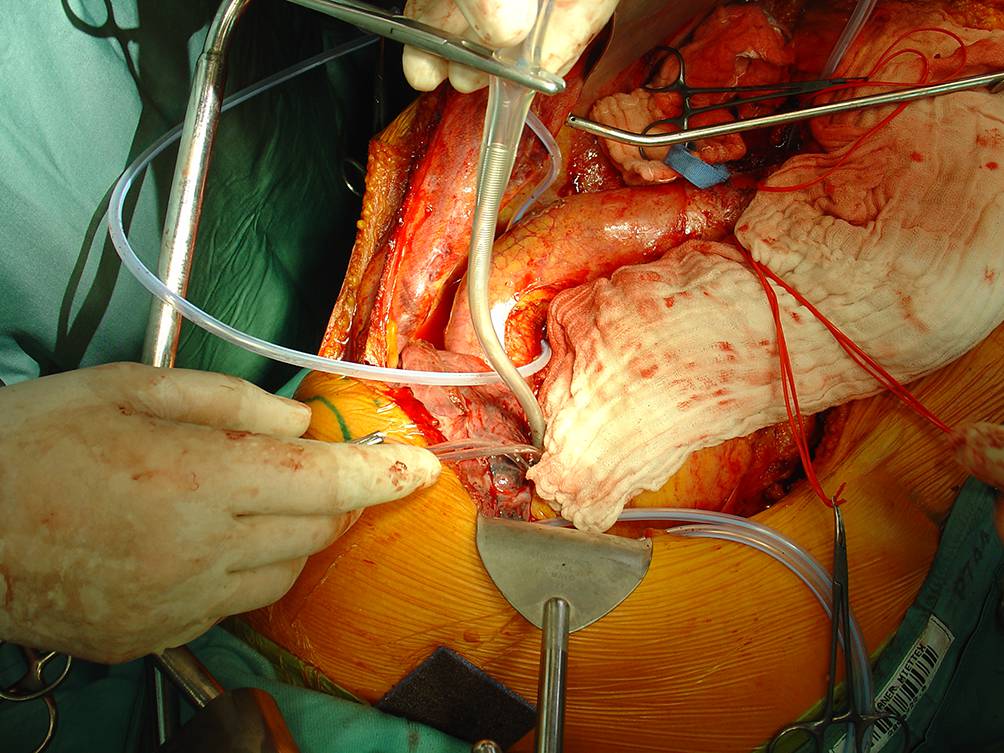

Für die chirurgische Behandlung von Typ-II-TAAA stehen Rohrprothesen mit vorgefertigten Seitenarmen für die Anastomosierung der 4 viszeralen Gefäße zur Verfügung (Abb. 2).

Abb. 2

Operationssitus nach Ersatz eines Typ-II-TAAA (thorakoabdominelles Aortenaneurysma) mit einer 4‑armigen Rohrprothese für die Anastomosen zu Truncus coeliacus, A. mesenterica sup. und beiden Nierenarterien